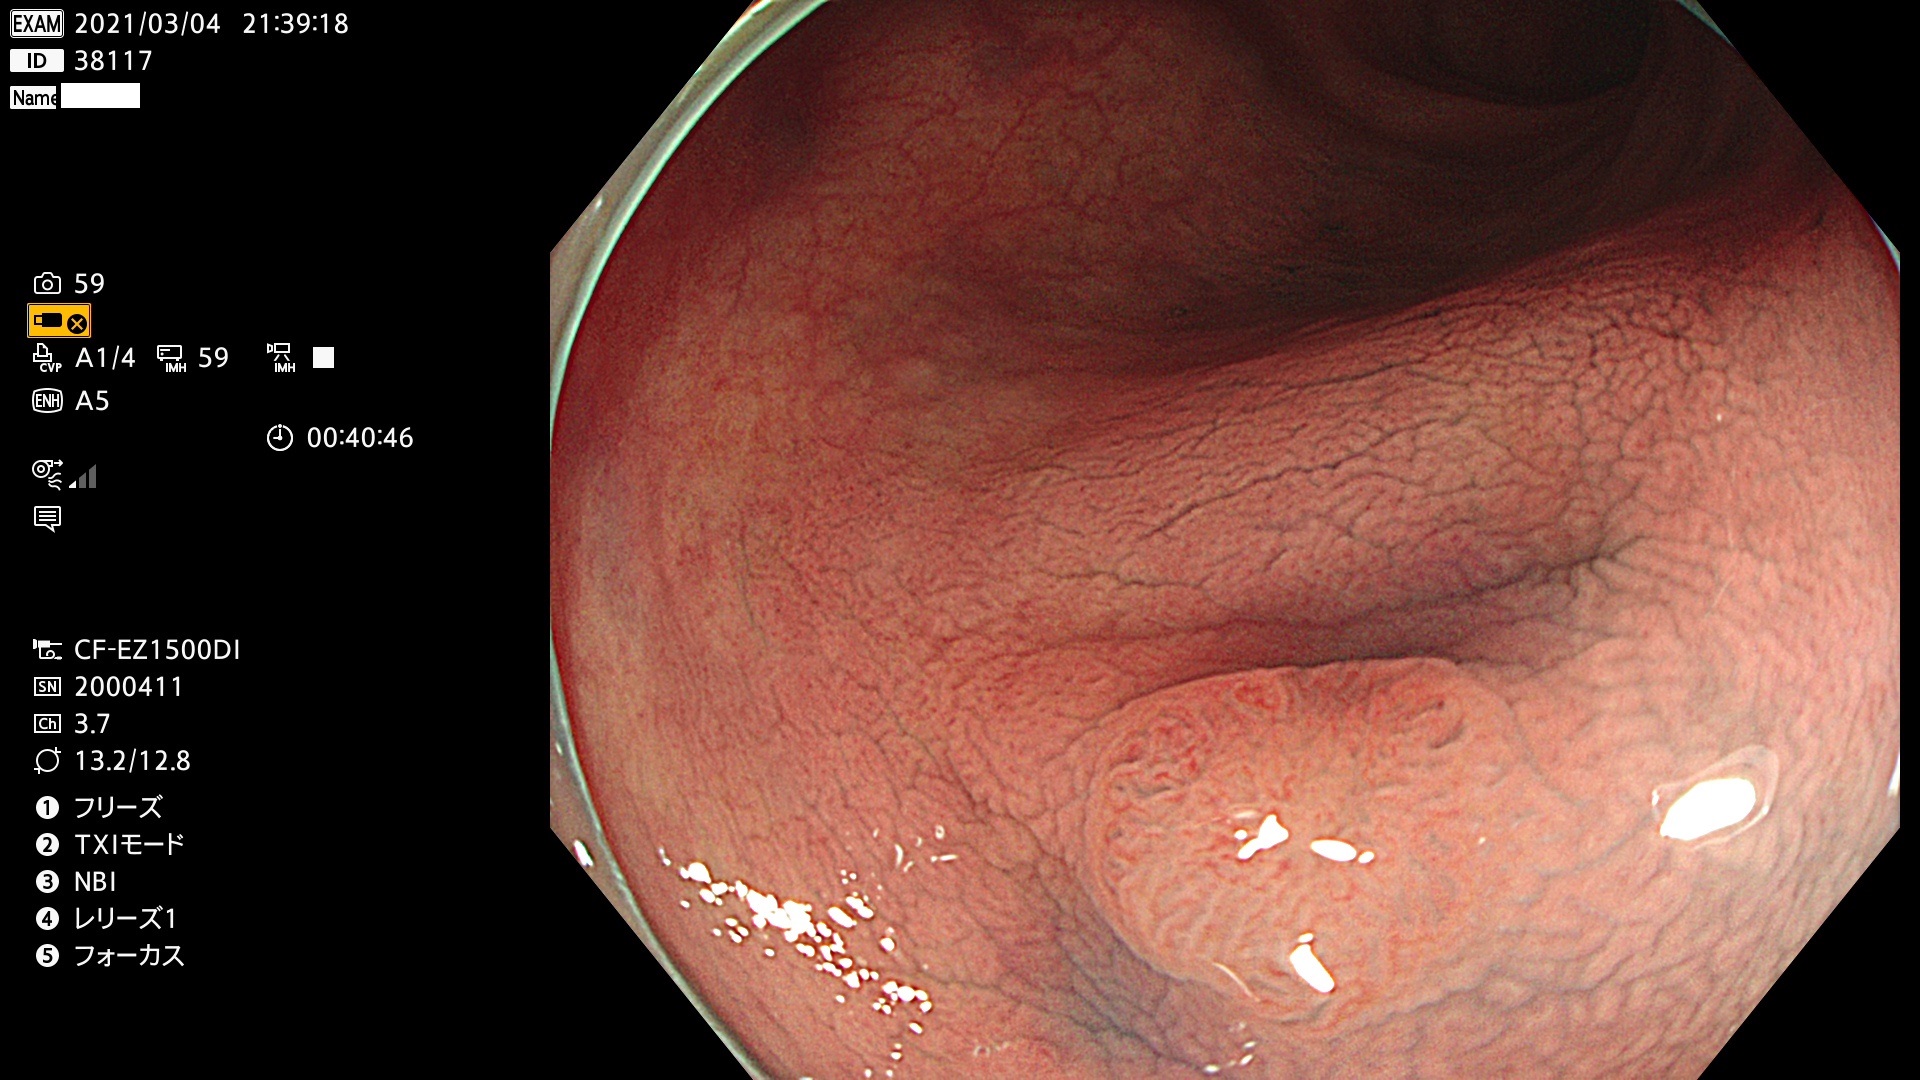

腺腫発見率 72 % (カルテ番号 38100〜38199の100名の方の検査結果で集計)大腸癌検診最新情報

以下のカルテ番号の方に腺腫(Adenoma,Group3〜5)が見つかりました(集計法)

38101 38103 38104 38106 38107 38108 38109 38110 38111 38112 38113 38114 38115 38117 38118 38122 38123 38124 38125 38126 38127 38128 38130 38131 38132 38135 38137 38138 38140 38141 38142(SSAPのみ) 38143 38144 38145 38146 38147 38148 38149 38150 38151 38152 38153 38154 38157 38158 38160 38161 38162 38164 38165 38166 38167 38168 38169 38172 38176 38177 38178 38181 38182 38183 38184 38187 38189 38190 38191 38192 38193 38194 38195 38196(SSAPのみ) 38198

発見困難で危険性の高い平坦型病変(上記100名より抽出) ![]()